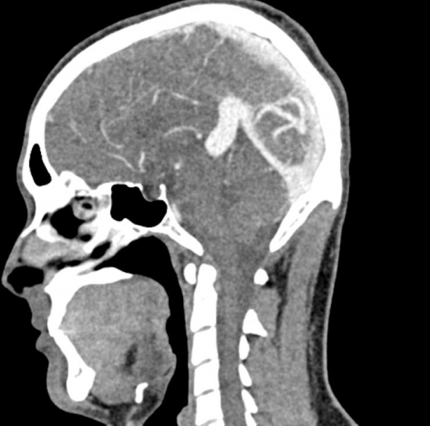

El maniquí de cabeza proporciona una simulación extremadamente realista de una angiografía por TC de cabeza y cuello (con contraste arterial) de un paciente con una malformación arteriovenosa en el lado derecho. El maniquí se entrega fiel a la escala original e incluye la columna cervical hasta la placa base de la quinta vértebra cervical.

Este fantasma se crea a partir de datos de pacientes reales y se fabrica con la última tecnología. Los huesos, vasos y tejidos blandos se muestran auténticamente con valores de TC realistas para todos los tejidos a un voltaje de tubo de 120 kVp en el TC. Si el maniquí se va a utilizar principalmente con otros voltajes de tubo (por ejemplo, 100 kVp), la calibración de los valores de CT se puede ajustar en consecuencia si es necesario. El fantasma proporciona contrastes de tejido realistas en las imágenes de rayos X. Los espacios aéreos se llenan con un material con aproximadamente -80 unidades Hounsfield.